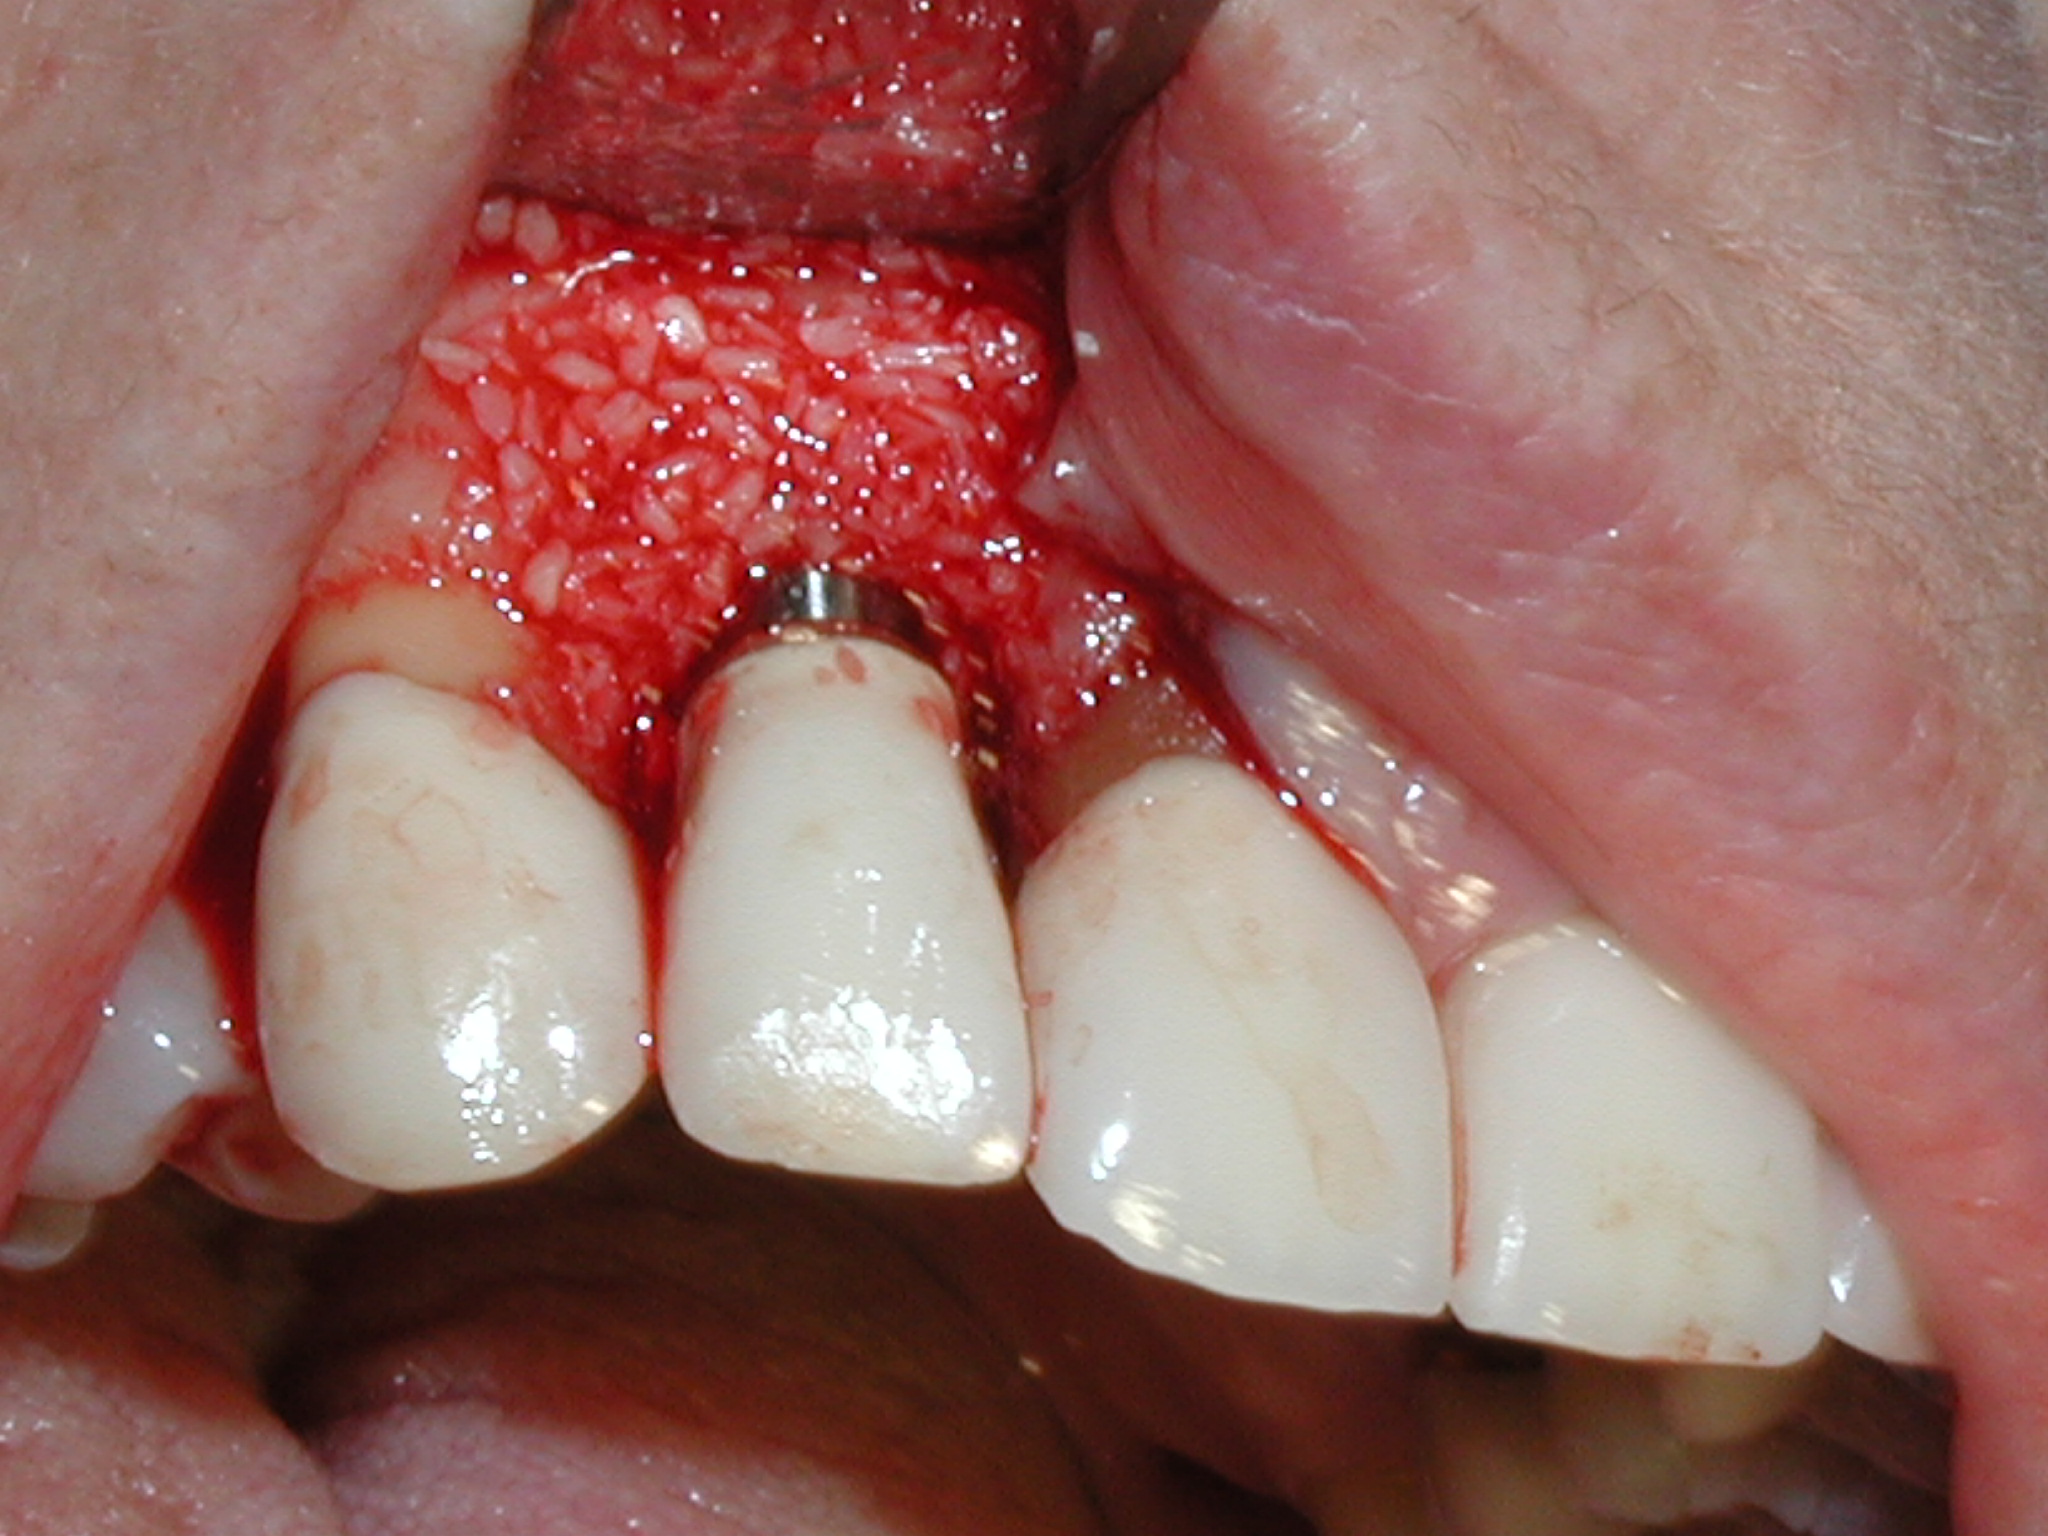

A guided bone regeneration (GBR) approach involving implant surface detoxification (Figure 2), placement of a bone graft combined with a barrier membrane (Figure 3 and Figure 4), and use of a systemic antibiotic has demonstrated the most predictable improvement in peri-implant parameters after destruction of supporting bone. GBR procedures demonstrated reductions in probing depth of 3.16 mm and 2.1 mm of radiographic bone fill in a recent systematic review and meta-analysis of 21 studies by Chan et al.21 Froum and Rosen22 defined a specific protocol based on reentry evaluation of previously treated peri-implantitis sites that included the use of rhPDGF-BB with freeze-dried mineralized bone and the addition of a resorbable membrane. Nonresorbable Gore-Tex® sutures were used to approximate the gingival tissue and were retained in place for 2 weeks. The patient was also kept on chlorhexidine for 2 weeks postoperatively. The reentry photographs from this report are quite impressive. However, the authors do caution the interpretation of re-osseointegration (Figure 5 and Figure 6).

Fig 2. Removal of cement and detoxification with tetracycline hydrochloride.

Figure 2

Fig 3. A freeze-dried bone allograft was placed.

Figure 3

Fig 4. A resorbable collagen barrier was placed.

Figure 4